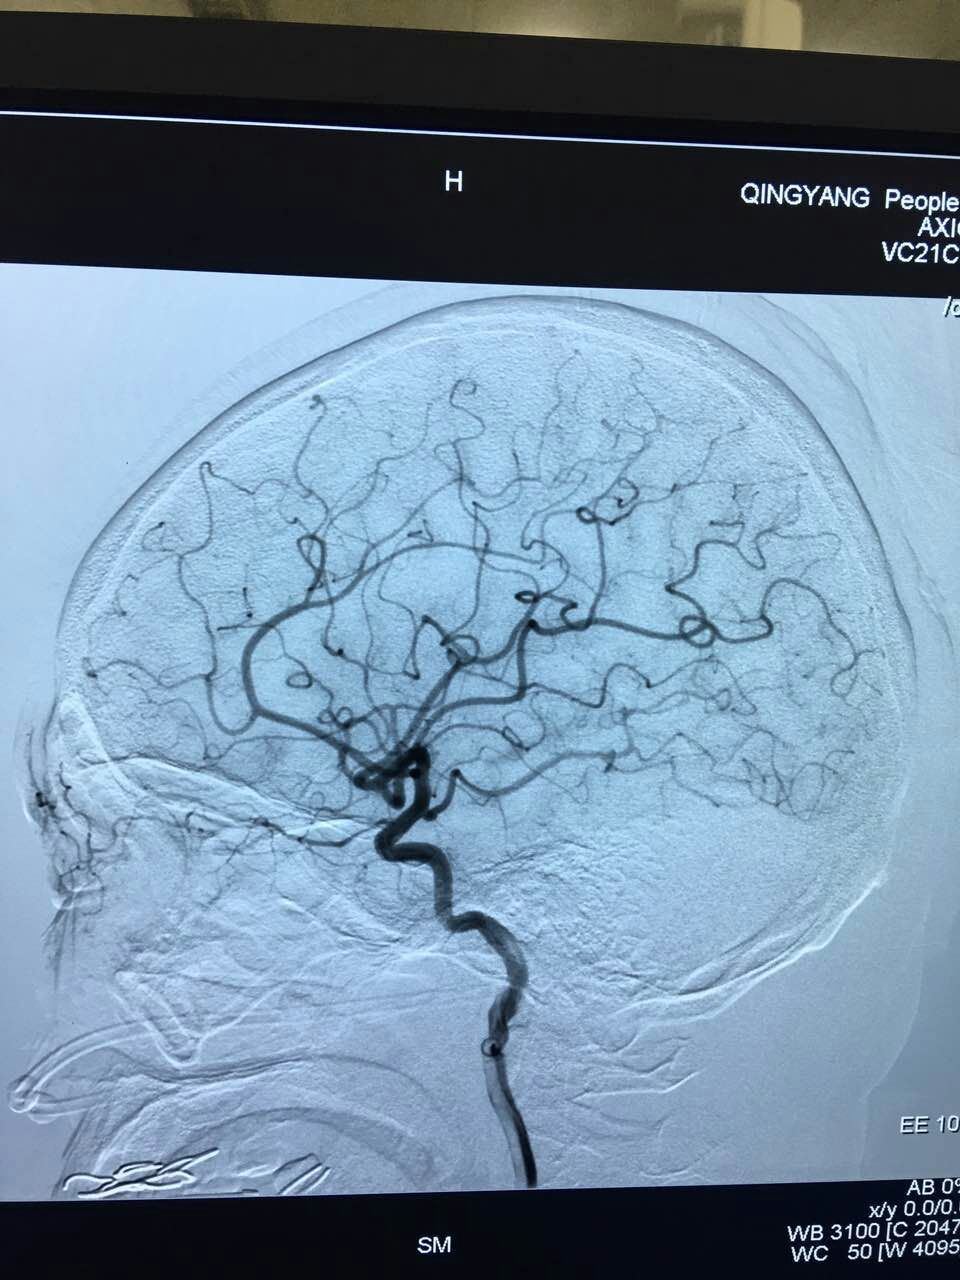

六、神經(jīng)外科微創(chuàng)與介入診療。(一)神經(jīng)內(nèi)鏡輔助下的顯微神經(jīng)外科手術(shù)是精準(zhǔn)醫(yī)療的一項(xiàng)關(guān)鍵技術(shù),在神經(jīng)內(nèi)鏡輔助下借助于內(nèi)鏡的照明系統(tǒng)和顯示系統(tǒng),完成以前術(shù)中難以發(fā)現(xiàn)的死角和高難度手術(shù),大大降低了腦出血患者和顱內(nèi)腫瘤患者的死亡率和致殘率。(二)腦血管造影及介入治療,通過(guò)腦血管造影了解腦血管形態(tài),進(jìn)一步發(fā)現(xiàn)顱內(nèi)動(dòng)脈瘤、血管畸形、血管狹窄等病因,采取相應(yīng)治療措施如顱內(nèi)放置血管支架、動(dòng)脈瘤栓塞、血管成型術(shù)或開(kāi)顱行動(dòng)脈瘤夾閉等。微創(chuàng)神經(jīng)外科與介入治療的開(kāi)展實(shí)施,在慶陽(yáng)市腦血管疾病、顱內(nèi)腫瘤等疾病診療方面開(kāi)辟了新天地。